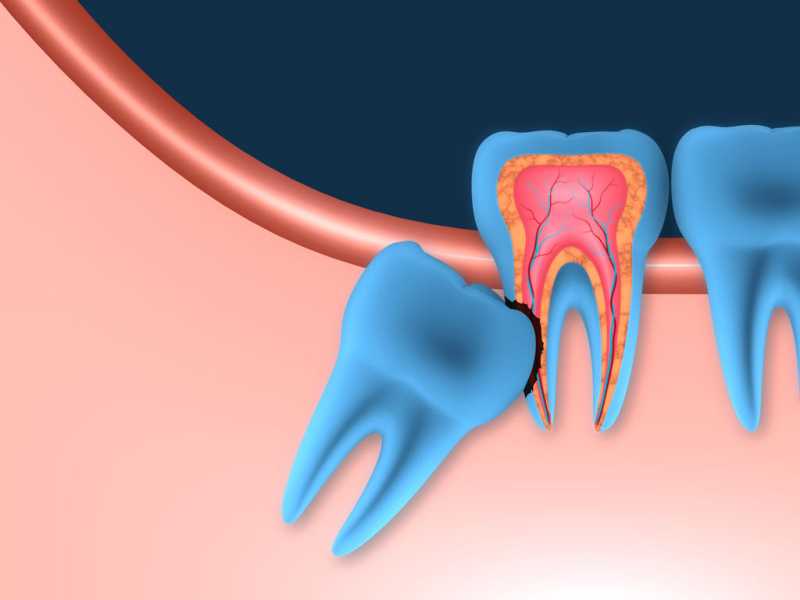

Inicio Especialidades Cirurgia